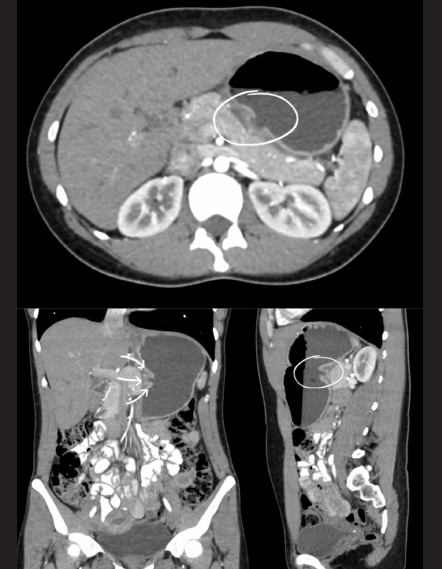

3. En la selección de imágenes multiplanares del estudio de tomografía computada abdominopélvica (figura 2), ¿qué es lo que se señala dentro del círculo y la flecha?

1. Nicho ulceroso gástrico en la curvatura mayor

2. Nicho ulceroso gástrico en la curvatura menor

3. Nicho ulceroso duodenal en la primera porción

4. Signo de la diana en la curvatura mayor

Figura 2 Selección de imágenes multiplanares del estudio de tomografía computada abdominopélvica con contraste oral (agua) e intravenoso, en fase arterial